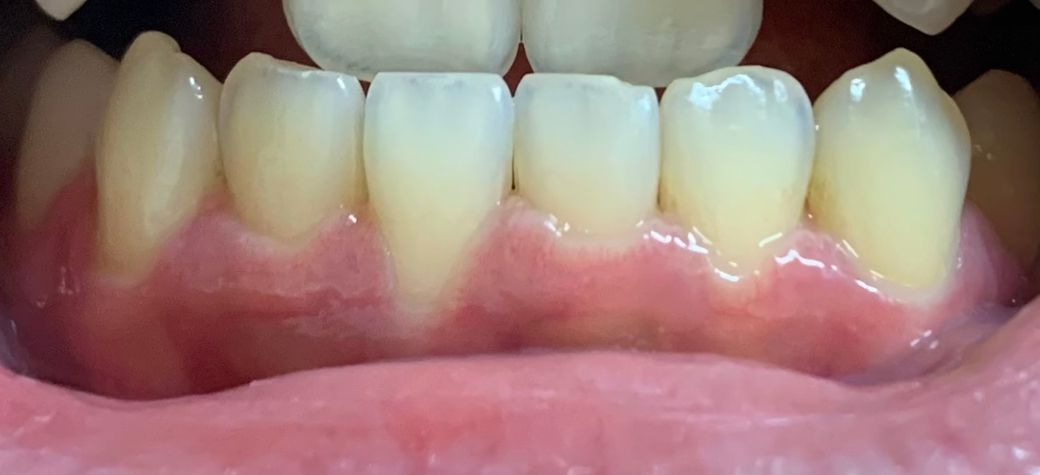

잇몸이 자라는건지 내려가는건지 모르겠어요..

아랫니 쪽 잇몸 라인이 점점 높낮이가 달라지길래 라인이 더 아래에 있는 쪽 잇몸이 내려간 건 줄 알았는데 예전 사진들을 보다보니까 다른쪽 잇몸이 자란 것 같다는 느낌이 들기도 하더라구요. 잇몸이 자랄 수도 있는건가요..?

치과 검진 주기적으로 가는데 올해 갔을때 선생님께서 혹시 복용하는 약이 있냐고 물어보시면서 아랫니쪽 사진?을 찍고 스케일링 받고 귀가했어서 대수롭지 않게 생각했었는데 착각인건지 한번 의식하고나니까 라인이 그때보다 좀 더 달라진 것 같기도 하고 궁금해서 여쭤봐여..

잇몸이 내려가고 뿌리가 많이 노출되어 있는 것으로 보이며 잇몸 염증이 있으면 생길 수 있는 증상입니다

앞니 하나만 잇몸이 퇴축된경우는 저 치아가 윗치아와 교합이 되서 힘을 많이 받아서 그러는거 같습니다. 잇몸이 내려가게되면 치아의 뿌리가 노출될수도 잇으면 치아가 시릴수도 잇습니다.

치아의 위치가 달라지거나 해당부위에 외부자극이 심하게 가해졌는경우 치은 퇴축이 일어날수 있습니다.

치아의 이동이 원인이라면 교정이 필요할수 있고 외부 자극이 원인이라면 자극이 되지 않도록 하시고 치은 이식을 할수도 있어요.